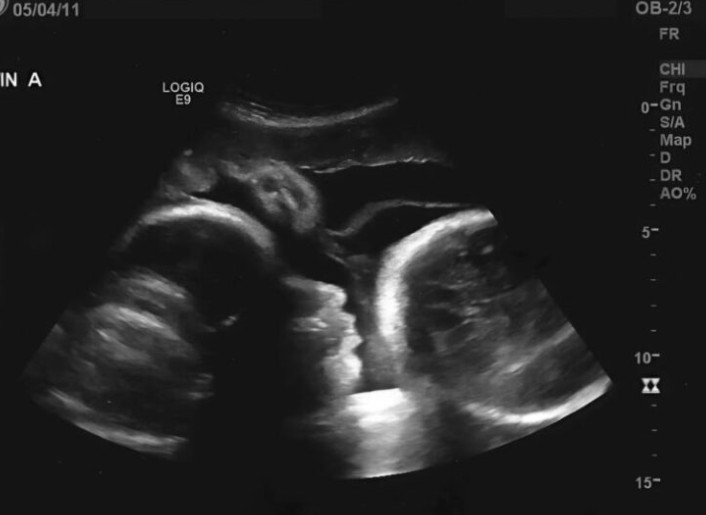

Men så snart hon klev in i undersökningsrummet förändrades allt. Den erfarna läkaren stirrade på ultraljudsbilden och bleknade plötsligt. Med skakig röst avslöjade han den brutala sanningen: Larisa var inte gravid. Det första testet hade gett ett felaktigt resultat.

Svullnaden i hennes buk kom inte från ett barn, utan från en enorm äggstockstumör som långsamt hade vuxit och börjat förtära hennes kropp inifrån.